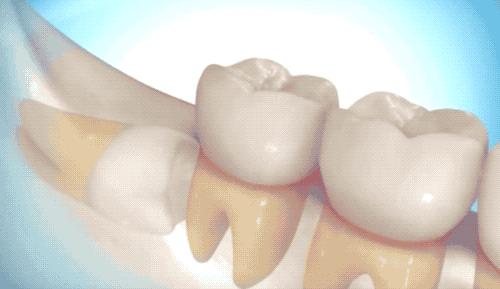

难度一

英雄模式

用高速旋转的涡轮机,把牙齿磨成两半,依次撬出来。